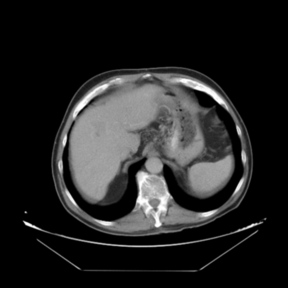

In addition to the previous measurements, the visual outcomes of two of the experiments are shown in Figures 3 and 4, whose purpose is to highlight the most illustrative differences (from a medical point of view) between the results provided by the compared methods. In Figure 3, we observe a normal size of the liver, with discretely irregular contours and homogeneous signal intensity. In hepatic segment II, there is a lesion of 40 mm of maximum axis, encapsulated and with well-defined contours and heterogeneous enhancement in arterial phase (after administration of intravenous contrast), suggestive of hepatocellular carcinoma (HCC). In this slice of the CT scan, we can also observe the aorta that shines in the arterial phase, the lower area of the stomach and the upper area of the spleen. In Figure 4, the liver has a normal size with discretely irregular contours in relation to changes due to chronic liver disease. In hepatic segment IV, a 36 mm diameter focal lesion is identified, which has arterial phase enhancement with a small area of necrosis of 13 mm; it corresponds to a HCC previously chemoembolized with partial necrosis. In this slice of CT, we can also observe the aorta, the gastric chamber and the spleen. When comparing the two methods under study, it can be seen how in Figure 3 the resulting registered datasets are very similar. However, looking closely, it can be noticed that in the right part of the image (left side of the patient) the shape and width of the structures corresponding to the stomach and the spleen in Figure 3(d) match better those in the reference dataset. Likewise, the part of the rib at the upper right of the image is more similar to the same region in the reference dataset by using the proposed method. Regarding the experiment shown in Figure 4, it can be easily appreciated how the geometrical matching (with respect to the reference dataset, Figure 4(a)) of the structures in the right side of the image (specially the gastric chamber) is visually more satisfactory in Figure 4(d). Moreover, the area of tumor necrosis which results from the proposed method is also slightly better aligned.

Arterial phase (reference dataset, R) Non-contrast phase (template dataset, T)

(a) Arterial phase (reference dataset, Failed to parse (MathML with SVG or PNG fallback (recommended for modern browsers and accessibility tools): Invalid response ("Math extension cannot connect to Restbase.") from server "https://mathoid.scipedia.com/localhost/v1/":): {\textstyle R}

)

(b) Non-contrast phase (template dataset, Failed to parse (MathML with SVG or PNG fallback (recommended for modern browsers and accessibility tools): Invalid response ("Math extension cannot connect to Restbase.") from server "https://mathoid.scipedia.com/localhost/v1/":): {\textstyle T}

Registered template, T_u (CR-based method) Registered template, T_u (proposed method)

(c) Registered template, Failed to parse (MathML with SVG or PNG fallback (recommended for modern browsers and accessibility tools): Invalid response ("Math extension cannot connect to Restbase.") from server "https://mathoid.scipedia.com/localhost/v1/":): {\textstyle T_\mathbf{u}}

(CR-based method)

(d) Registered template, Failed to parse (MathML with SVG or PNG fallback (recommended for modern browsers and accessibility tools): Invalid response ("Math extension cannot connect to Restbase.") from server "https://mathoid.scipedia.com/localhost/v1/":): {\textstyle T_\mathbf{u}}

(proposed method)

Figure 3. Visual outcomes of experiment 1 (slice 9): registration of arterial and non-contrast phases of patient 1